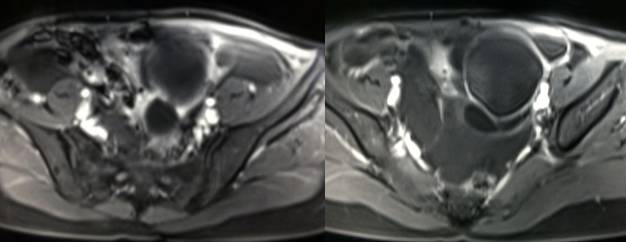

病理结果:黄体血肿

黄体血肿为正常排卵过程中,卵泡层破裂,引起出血,较多的血液潴留在卵泡或黄体腔内形成血肿。

正常黄体直径为15mm左右,以后转变为白体,并在下一个周期的卵泡期自然消退。若黄体内出血量较多,则形成黄体血肿,或称黄体内出血,出血性黄体。黄体血肿多为单侧,一般直径为40mm,偶可达100mm,黄体血肿被吸收后可导致黄体囊肿,较大的血肿破裂时可出现腹腔内出血,剧烈腹痛、少量阴道流血和腹膜刺激征,不易与宫外孕区别。

黄体血肿晚期:血液吸收后囊肿变小,转变为白体,内部回声呈实性稍高回

声,与周围卵巢策划分界不清,面靠彩超显示其周围环状血流判断,当血液完全吸收后形成黄体囊肿,囊壁变得光滑,与卵巢其他囊肿难以区分。

根据时间不同MR信号也有所不同,TIWI脂肪抑制序列可以鉴别脂肪和出血。

巧克力囊肿:常呈多发的单囊或多囊改变,病灶大小不等,囊壁厚薄不均,囊内信号复杂,囊内或各囊腔间血液因出血时期不同,信号常呈多样性,囊肿内反复出血、破裂,形成相互粘连的多房性囊肿,是其较为特征性的表现。

在鉴别卵巢畸胎瘤、出血性囊肿或巧克力囊肿时,MR 脂肪抑制T1WI 可明确肿块内高信号成分是脂肪还是出血,同时由于脂肪策划与非脂肪策划的共振频率不同,在两者交界处沿磁场频率编码方向出现化学位移伪影,但出血性囊肿与巧克力囊肿的鉴别有时较为困难。